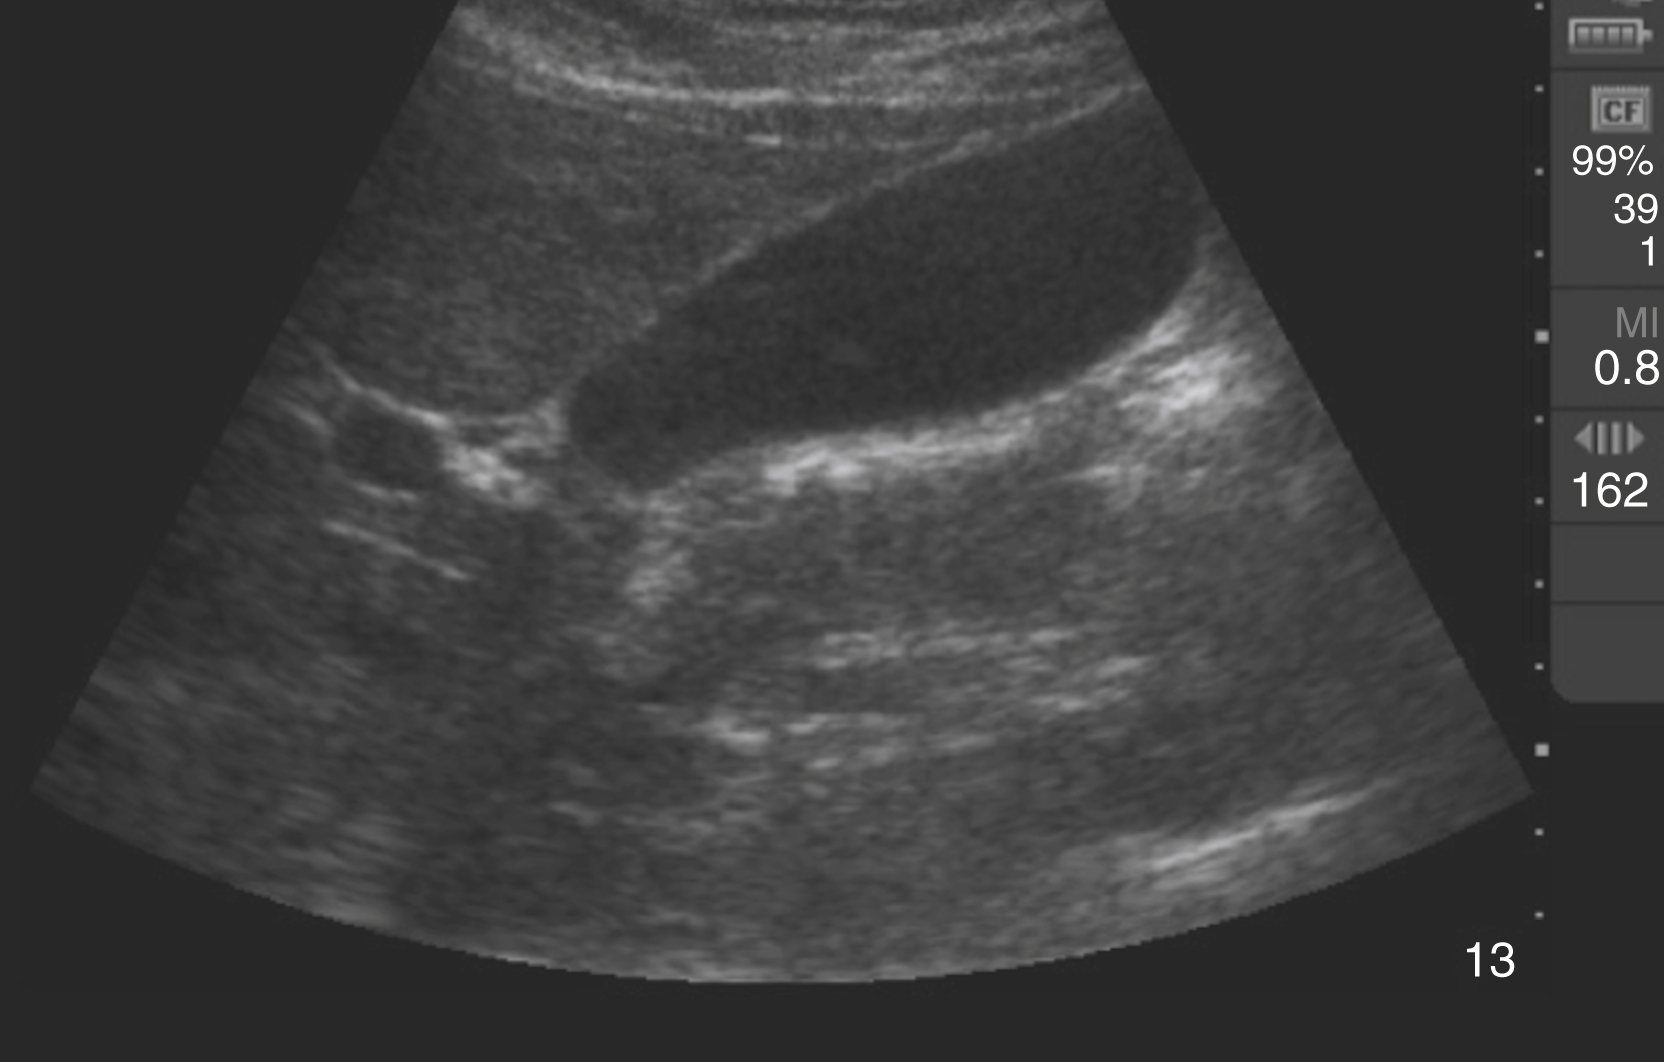

The FAST examination technique uses a low-frequency broadband transducer (2–6 MHz) to evaluate dependent peritoneal spaces, pleural spaces, and the pericardium for free fluid, which in the trauma patient is presumed to be blood. There are four main components of the basic FAST examination: (1) the right upper quadrant (RUQ) view, (2) the left upper quadrant (LUQ) view, (3) the pelvic view and (4) the cardiac view ( Fig. e3.1 ). The E-FAST includes anterior chest views to evaluate for pneumothorax. The RUQ view evaluates for fluid in the thorax (above the diaphragm) ( Video e3.1 ), hepatorenal space (Morison pouch) and the paracolic gutter (inferior edge of the liver and right kidney) ( Video e3.2 ), moving cephalad to caudad. The LUQ view, found slightly more superior and posterior than the RUQ, should mimic the RUQ views, but also include the subdiaphragmatic space, because free intraperitoneal fluid tends to accumulate here initially. The pelvis should be evaluated in the transverse and longitudinal planes, where fluid may be detected deep to the uterus (in females) or in the retrovesical space (in males) ( Video e3.3 ). The cardiac evaluation can be performed in either the subcostal (or subxiphoid) or parasternal window ( Video e3.4 ). Evaluation for pneumothorax uses a low or high-frequency transducer at a shallow depth, placed along the anterior chest wall and will be discussed in more detail in subsequent sections.

Negative FAST images. (A) Subxiphoid view with no pericardial effusion. (B) Negative RUQ view showing the thorax and hepatorenal space without the paracolic gutter visualized. There is mirroring and loss of the spine, indicating a negative thorax. (C) Negative paracolic gutter area by the liver tip in the RUQ view. (D) LUQ view showing negative thorax, as in B, and splenorenal space. (E) Negative transverse bladder view. (F) Negative sagittal bladder view.

Typically, free fluid is anechoic, but it can have echogenicity if active extravasation, a blood clot, or bowel contents are present within the fluid. Compared with other fluid-filled structures in the abdomen and pelvis, peritoneal free fluid generally has sharp pointed edges and an irregular shape, whereas most visceral or vascular structures have intrinsically smooth oval or round contours. The volume of fluid required for a positive US study depends on the site of injury, sonographic window, and experience of the operator, but 250 mL or more is generally visible, and nearly 600 mL of fluid is required for a positive upper quadrant window. With pericardial fluid, once a certain volume is reached, the pressure in the pericardial space increases dramatically, resulting in cardiac tamponade. Generally, at least 50 mL of fluid is required to cause hemodynamic compromise in a patient without prior pericardial inflammation ( Fig. e3.2 ).

Positive FAST images. (A) Positive RUQ view showing a thin stripe of fluid in the hepatorenal space. The thorax is negative and paracolic gutter not visualized. (B) Positive LUQ view showing a hemothorax and splenorenal space. There is loss of mirroring and continuation of the spine. (C) Subxiphoid view showing a pericardial effusion circumferentially. (D) Positive transverse bladder view with free fluid noted posterior to the bladder on the right of the image.